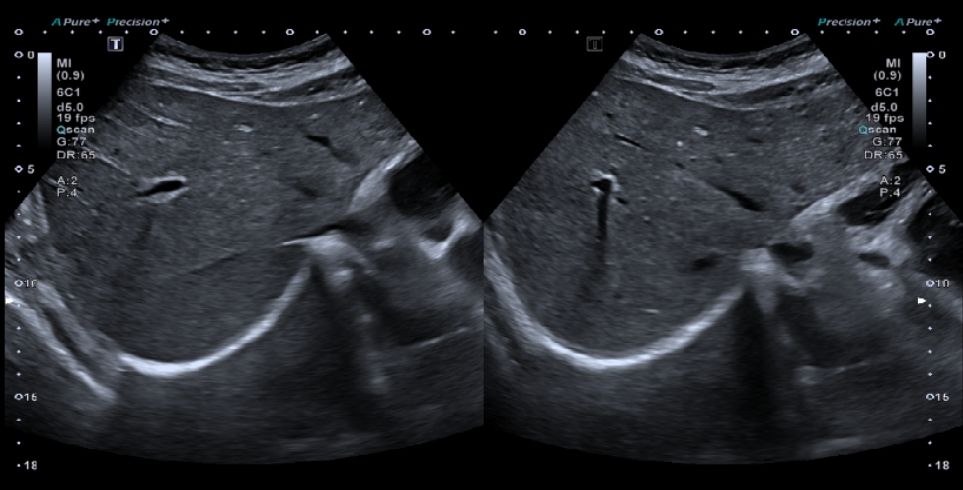

A ecografia abdominal superior é um exame de imagem de primeira linha para a avaliação dos órgãos do abdómen. É simples, rápido e não invasivo, permitindo visualizar em tempo real estruturas como o fígado, vesícula biliar, pâncreas, rins e baço. Por não recorrer a radiação, é considerado seguro em todas as idades, incluindo em grávidas e crianças.

A ecografia abdominal utiliza ultra-sons de alta frequência emitidos por uma sonda, que atravessam os tecidos e são refletidos, originando imagens detalhadas dos órgãos.

Durante a ecografia, o(a) paciente permanece deitado(a) numa maca, numa sala pouco iluminada para facilitar a visualização das imagens. O médico aplica um gel transparente sobre a pele do abdómen, que permite a correta transmissão dos ultra-sons e o deslizar da sonda.

As imagens são obtidas em tempo real e avaliadas pelo médico especialista em imagiologia. O exame dura geralmente entre 15 e 30 minutos.

A ecografia abdominal superior permite observar com detalhe diferentes órgãos e estruturas do abdómen. É útil para identificar alterações no fígado, como quistos, nódulos ou sinais de doença hepática difusa, e avaliar a vesícula biliar, detetando cálculos (pedras) ou inflamações. Também possibilita o estudo do pâncreas, revelando massas ou inflamações, bem como do baço, verificando o seu tamanho e possíveis lesões.

Além disso, permite identificar dilatações das vias biliares ou urinárias, líquidos livres no abdómen e alterações vasculares através do Doppler. Este exame é muitas vezes o primeiro passo no estudo de sintomas abdominais, sendo também essencial no seguimento de doenças crónicas e no acompanhamento após cirurgia abdominal.